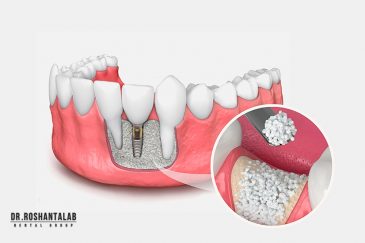

🔸کاشت ایمپلنت فلپ لس یا بدون جراحی و بدون بخیه زیر سه دقیقه

تجربه کاشت دندان دیجیتال و بدون درد در ۳ دقیقه! استفاده از برترین برندها زیر نظر جراح، با هزینه مناسب و خدمات کامل از کاشت دندان تا روکشارتودنسی دندان